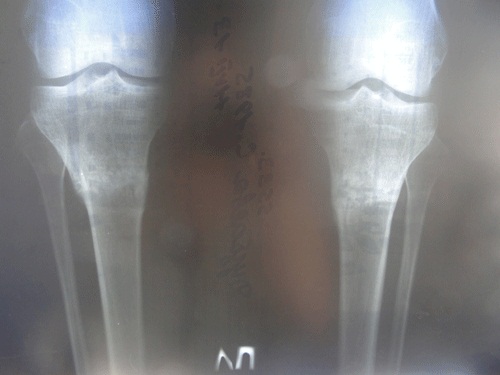

у меня все хорошо,каждый день радуюсь своими ножками) спасибо Вам большое за всё! высылаю Вам фото рентген-снимков через 2 мес после снятия аппаратов. 4 июля было ровно два месяца, на той неделе не успела сделать.снимки сделала сегодня,11 июля.жду Ваших комментарий. по почте снимки нужно высылать или нет?